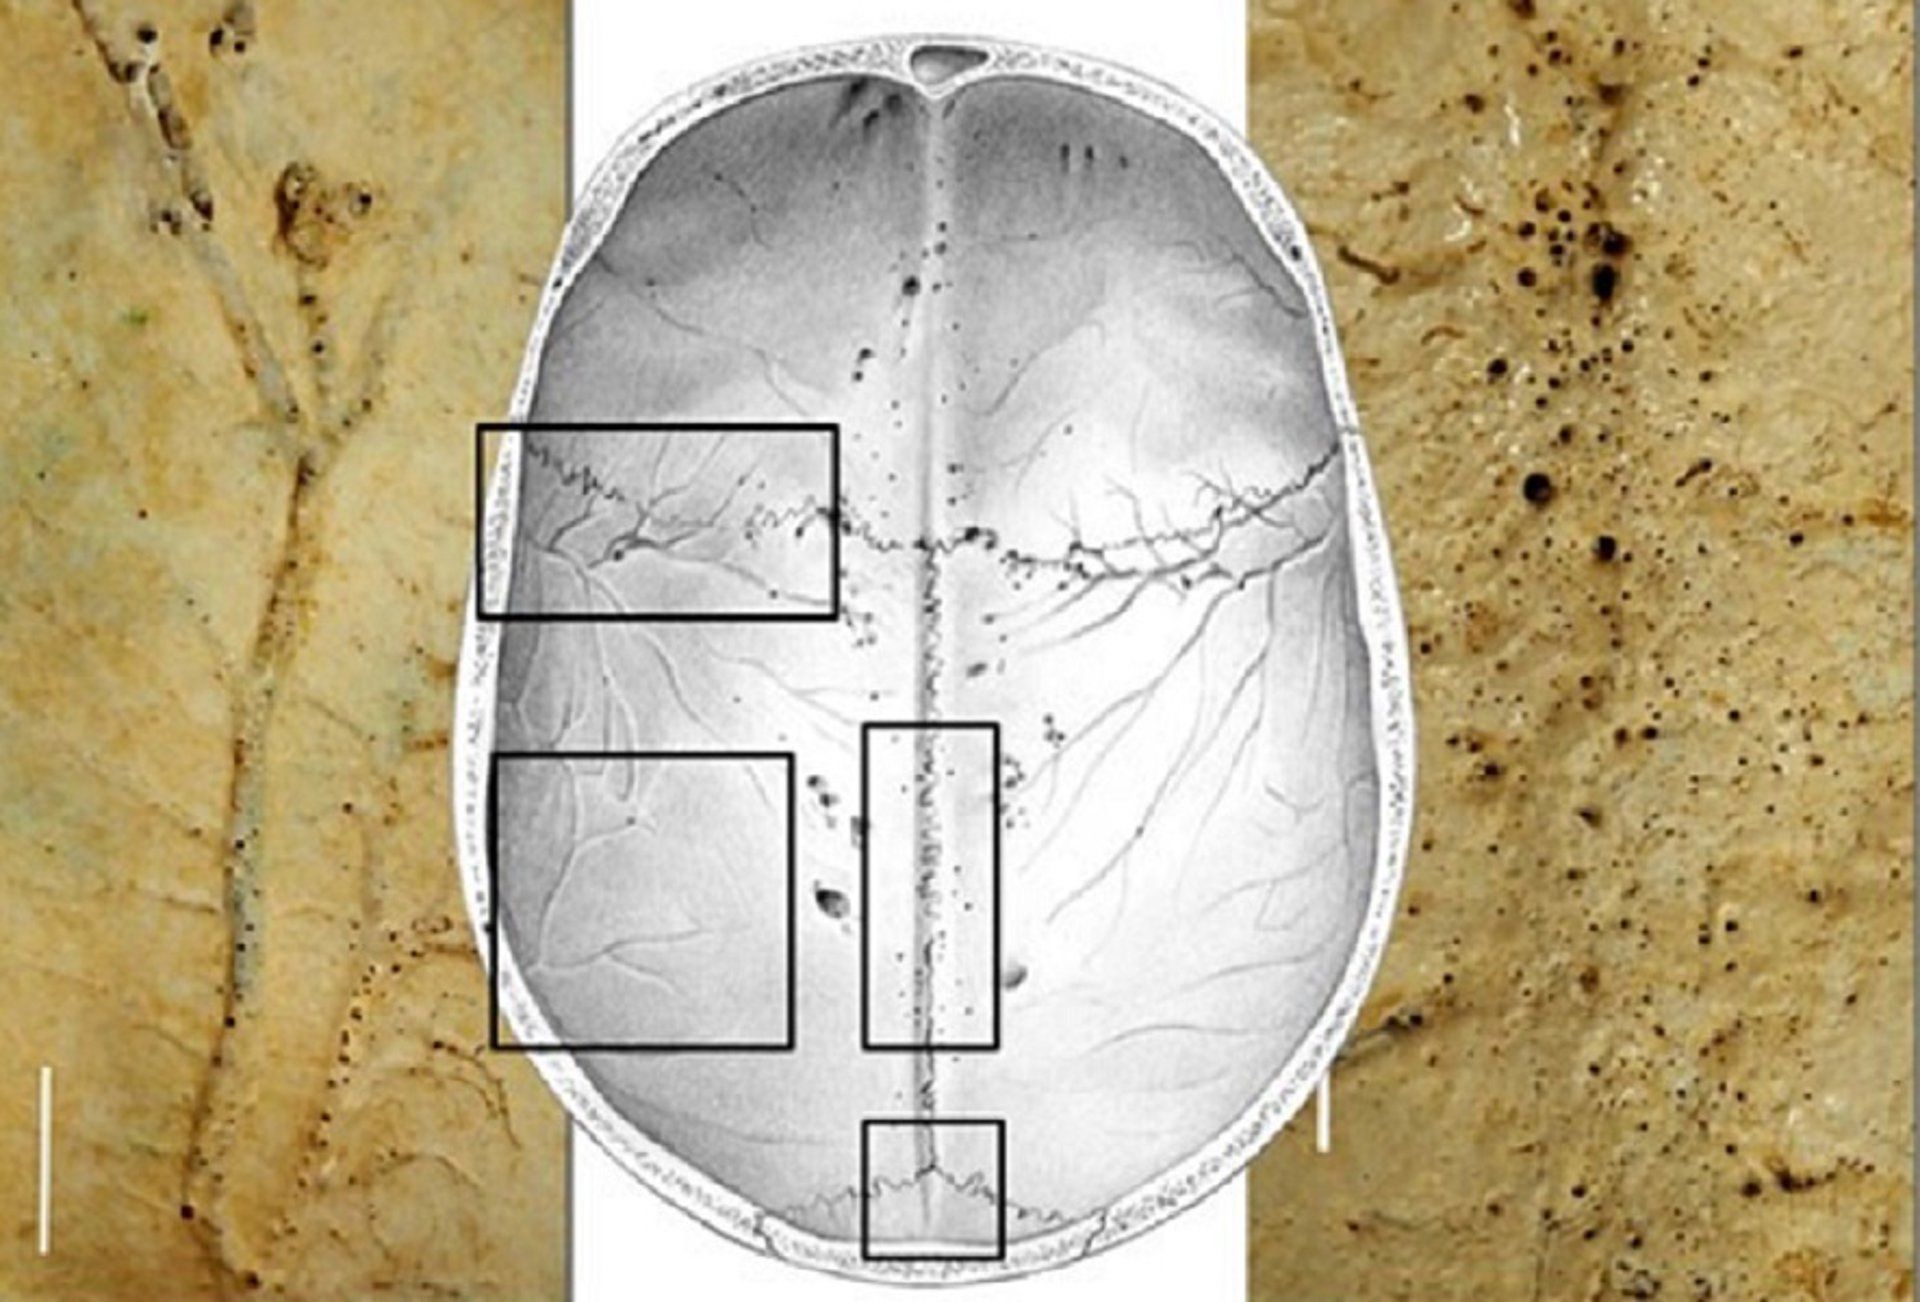

Los microforámenes son conductos vasculares diminutos, de entre 0,03 y 2 milímetros, que atraviesan los huesos craneales desde su capa interna hasta la superficie en contacto con las meninges. «La presencia de estos canales se mencionó en la literatura científica en los años 90, y hace tres años se reveló que estaban implicados en la respuesta inmunitaria e inflamatoria del cerebro, pero hasta hoy no teníamos una descripción formal de su apariencia, tamaño y distribución en el cráneo humano», explica Emiliano Bruner.

Anteriormente, estas estructuras se habían detectado solo mediante histología o tomografía computerizada. Ahora, este estudio ofrece una descripción detallada de su morfología y distribución a través de la observación directa con herramientas simples como lupas.

Bruner observó que la distribución de estos microcanales varía significativamente entre individuos, donde algunos cráneos mostraban solo unos pocos, mientras que otros tenían cientos. Además, «las variaciones individuales son notables, y cada sujeto tiene un patrón único en términos de tamaño y distribución de los microcanales», señala el investigador.

Las áreas con mayor densidad de estas estructuras se encuentran en la parte posterior de los huesos parietales y a lo largo de la sutura sagital. También se observaron numerosos microconductos en las áreas por donde pasan las arterias meníngeas medias.